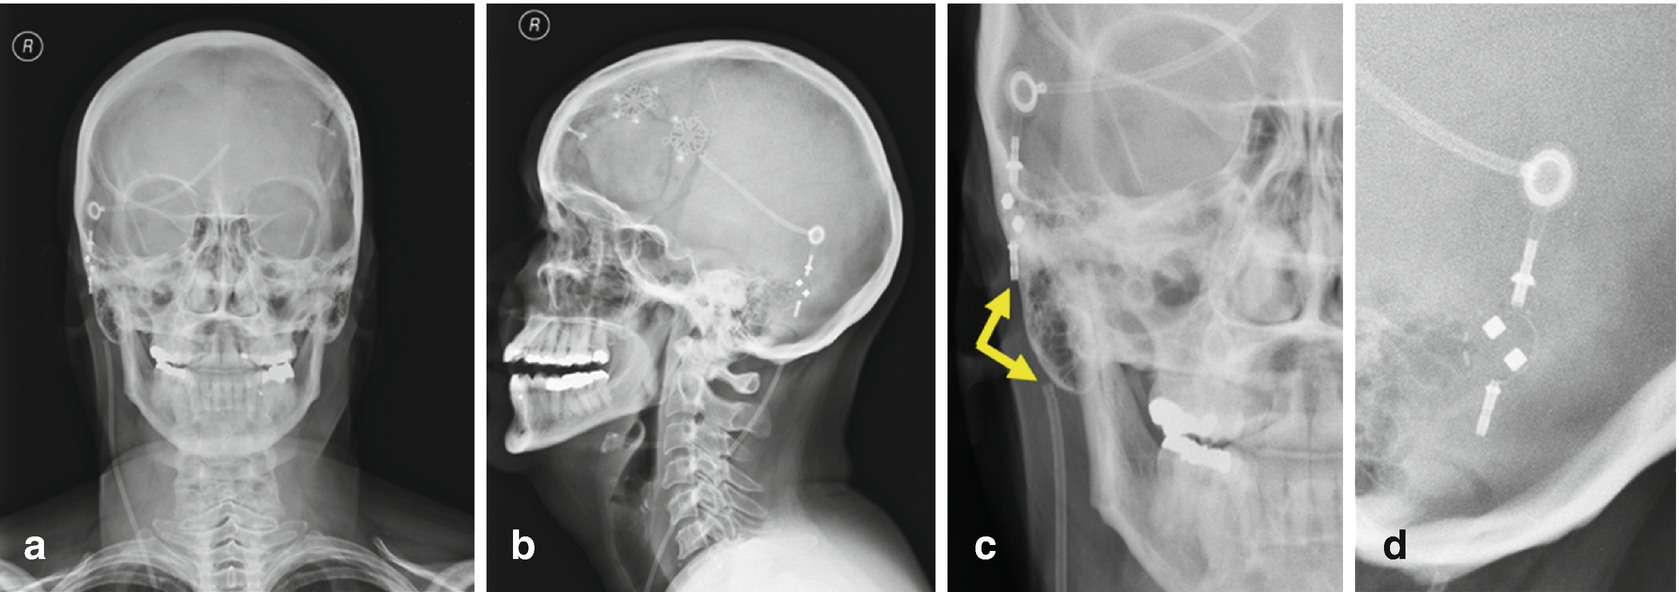

Radiologic Identification Of Vp Shunt Valves And Adjustment Pediatric Neurosurgery Leipzig